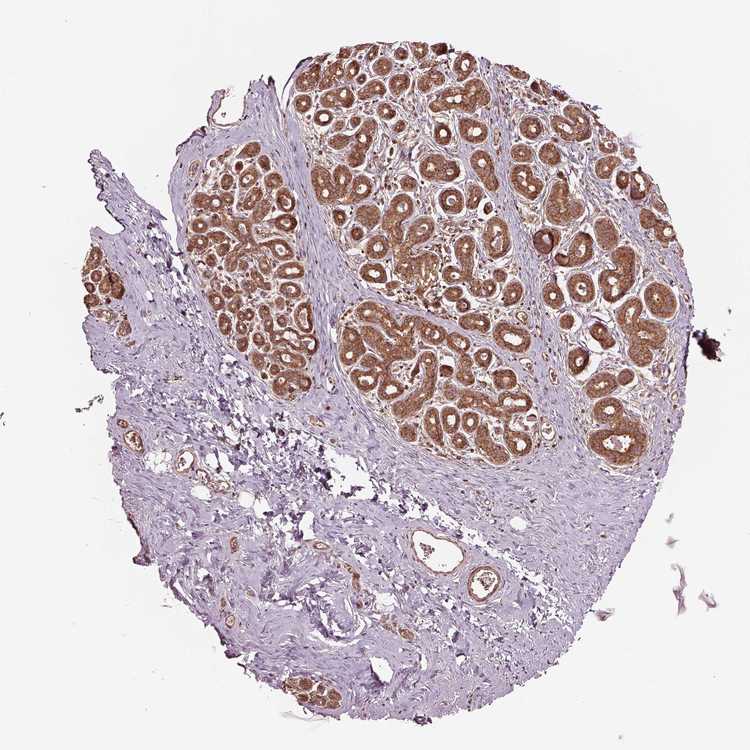

BREAST - Antibody stainingi

Antibody staining in the annotated cell types in the current human tissue is reported as not detected, low, medium, or high, based on conventional immunohistochemistry profiling in selected tissues. This score is based on the combination of the staining intensity and fraction of stained cells.

Each image is clickable and will lead to virtual microscopy that enables deeper exploration of all samples and also displays staining intensity scores, fraction scores and subcellular localization as well as patient and tissue information for each sample.

Antibody HPA017961

Adipocytes Not detected

Glandular cells High

Myoepithelial cells Medium